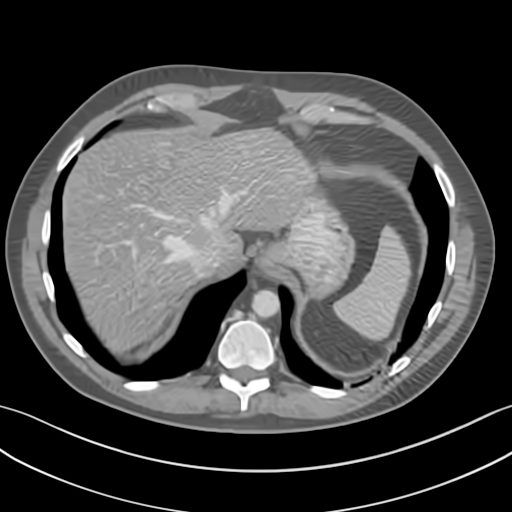

To demonstrate the effectiveness of the proposed network, we perform the qualitative comparisons over three representative abdominal images presented in Figs. 3, 5 and 7. For better evaluations of the image quality with different denoising models, zoomed regions-of-interest (ROIs) are marked by red rectangles and shown in Figs. 4, 6 and 8 respectively. Note that all results from different denoising models focus on two aspects: content restoration and noise-reduction. All CT images in axial view are displayed in the angiography window [-160, 240]HU.

The real NDCT images and corresponding LDCT images are presented in Figs. 3a and 3b. As observed, there are distinctions between ground truth (NDCT) images and LDCT images. Figs. 3a and 7a show the lesions/metastasis. Fig. 5a presents focal fatty sparing/focal fat. In Figs. 4a, 6a and 8a, these lesions can be clearly observed in NDCT images; in contrast, from Figs. 4b, 6b, and 8b, it can be seen that the original LDCT image is noisy, and lacks structural features for task-based clinical diagnosis. All adopted denoising models suppress noise to some extent.